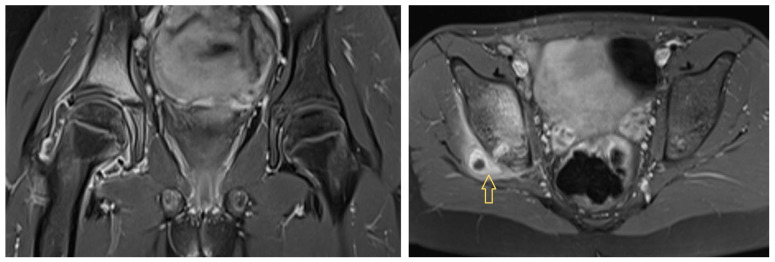

Background: In paediatric osteoarticular infections, microorganism detection is unsuccessful in up to 55% of cases, which is not satisfactory for targeted antibiotic therapy. In particular, anaerobic fusobacteria may be underdiagnosed owing to a lack of knowledge about their properties. Methods: Based on three of our own cases and a systematic literature review regarding paediatric osteoarticular fusobacterial infections, we extracted characteristic variables and synthesised them in terms of frequencies and mean comparisons. We followed the CARE and PRISMA guidelines. Results: In our three patients with hip area infections (aged 11, 12, and 16 years; two males and one female; two with Fusobacterium nucleatum [FNU] and one with Fusobacterium necrophorum [FNE]), we only detected FNU with PCR. The patient with an FNE infection showed a septic and protracted course with six surgical interventions and secondary coxarthrosis during the follow-up. The FNU infections were milder and healed without sequelae. In the literature, there are no articles with more than 3 cases; overall, we identified 38 case reports and 3 case series with a total of 45 patients. Across all synthesised cases (73% boys), the age was 9.2 ± 4.1 years. Most patients (42%) were affected by hip joint arthritis, with or without accompanying acetabular or femoral osteomyelitis, followed by knee joint arthritis, with or without osteomyelitis, in 24% of patients. In 49% of cases, there was an ear, nose, and throat focus. Depending on the affected structure, arthrotomy (33%), arthroscopy (11%), bone (24%), and soft tissue (9%) debridement were performed, with 34% of the procedures having to be performed several times. Penicillins, metronidazole, and clindamycin were the most used antibiotics. In 32 cases (71%), the authors reported healing without sequelae. Conclusions: When samples are collected in the operating theatre for paediatric osteoarticular infections, orthopaedic surgeons should also ensure correct anaerobic sampling and consider the possibility of performing PCR. A typical child with an osteoarticular fusobacterial infection is a boy of approximately 10 years of age with an infection in the hip area and a previous infection in the ENT area.